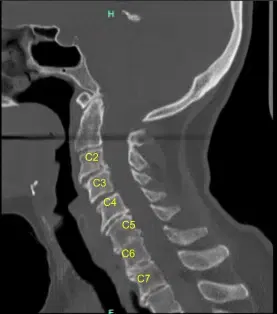

The CT scan was suggestive of Degenerative disc disease at multiple levels. The patient gave informed consent, understanding all of the risks, benefits, and alternatives to surgery. We discussed treatment options and agreed to go ahead with Anterior Cervical Discectomy and fusion C3 to C6.

The patient made a full recovery and continued to take part in regular daily activities. A postoperative cervical spine 2 or 3 view x-ray was ordered and the sagittal view is shown below.